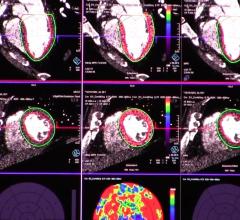

This channel contains news about the Society of Cardiovascular Computed Tomography (SCCT), including coverage of its annual meeting and links to recently released practice guidelines. SCCT is a leading resource for the subspecialty of cardiac computed tomography angiography (CTA or CCTA).

The Society of Cardiovascular Computed Tomography (SCCT) annual meeting offers an in-depth review of all aspects of ...

Here is a recap of some of the top trends and new technology at the Society of Cardiovascular Computed Tomography (SCCT) ...